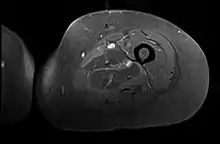

Creatine kinase may be normal or increased probably depending upon the stage of the condition when sampling is undertaken. ESR is elevated. Planar X-ray reveals soft tissue swelling and may potentially show gas within necrotic muscle, Bone scan may show non specific uptake later in the course. CT shows muscle oedema with preserved tissue planes (non-contrast enhancing). MRI is the exam of choice and shows increased signal on T2 weighted images within areas of muscle oedema. Contrast enhancement is helpful but must be weighed against the risk of Nephrogenic Systemic Fibrosis as many diabetics have underlying chronic kidney disease. Arteriography reveals large and medium vessel arteriosclerosis occasionally with dye within the area of tissue infarction. Electromyography shows non specific focal changes.

Axial fat suppressed T2 weighted MRI image showing hyperintense signal and enlargement of the left thigh adductor muscle group in diabetic myonecrosis.